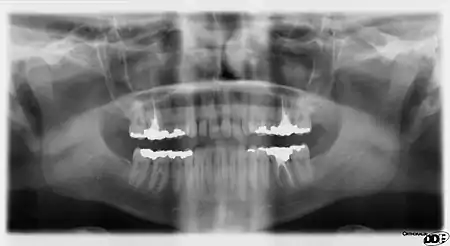

Panoramic films

Panoramic films are extraoral films, in which the film is exposed while outside the patient's mouth, and they were developed by the United States Army as a quick way to get an overall view of a soldier's oral health. Exposing eighteen films per soldier was very time consuming, and it was felt that a single panoramic film could speed up the process of examining and assessing the dental health of the soldiers; as soldiers with toothache were incapacitated from duty. It was later discovered that while panoramic films can prove very useful in detecting and localizing mandibular fractures and other pathologic entities of the mandible, they were not very good at assessing periodontal bone loss or tooth decay.[21]